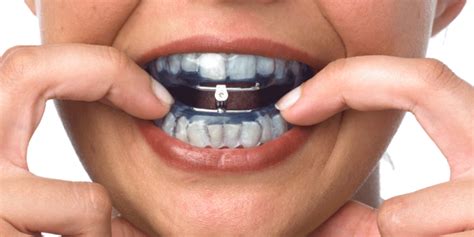

Diagnosi e terapia sindromi da apnee ostruttive notturne (Osas)

E' una patologia che sta diventando una vera e propria piaga sociale in quanto da statistiche potrebbe essere causa di circa il 20% degli incidenti automobilistici e che quindi coinvolge anche molti lavoratori nel settore dei trasporti.

I pazienti ,non potendo avere un sonno sufficiente e regolare per motivi anatomici e disfunzionali delle prime vie aeree, vanno incontro durante le ore diurne a narcolessie (addormentamento improvviso e scarsa lucidità nei riflessi) ed a frequenti cali di attenzione senza contare che le apnee che avvengono durante la notte (arresto del sistema respiratorio momentaneo ma ripetuto) possono essere concausa di malattie cardio vascolari e ictus.

Nella nostra rete ospedaliera esiste un protocollo diagnostico e terapeutico che coinvolge la figura del medico del sonno (OtorinoLaringoiatra), dello pneumologo ,del cardiologo , del neurologo e non per ultimo in ordine di importanza dell'odontostomatologo il quale , nelle forme lievi o moderate , puo' approntare dispositivi funzionali (apparecchi orali) che spostando in avanti la mandibola possono migliorare o risolvere questa problematica disfunzionale ed il russamento notturno.

![]() | ![]() |